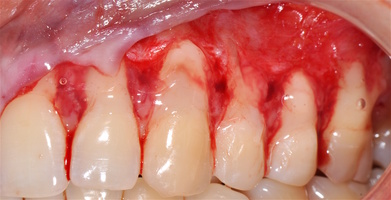

В области от 1.6 до 2.6 и от 3.6 до 4.6 все зубы имеют некариозные поражения разной степени, такие как эрозии эмали и клиновидные дефекты, вовлекающие в процесс ткани эмали и дентина. Подвижности зубов не выявлено (рис. 1а-е) [9].

При анализе и описании компьютерной конусно-лучевой томографии (рис. 2а-г) была выявлена генерализованная первичная дегисценция вестибулярной пластинки кости от 1/2 до 3/4 длины корней зубов, зубной ряд целостный, все зубы витальны, кариозных поражений нет. Тип кости 1-2 (Lechkolm и Zarb, 1983), первичная дегисценция вестибулярной костной пластинки превышает пределы возрастной атрофии.

1. Генерализованные рецессии в области нижней челюсти оперировались в один этап все 12 зубов, фронтальный участок с аутотрансплантатом от 3.2 до 4.2 зубов. А дистальные участки от 3.6 до 3.3 и от 4.6 до 4.3 зубов с использованием пластического материала ТМО (dura mater) (рис. 4а-з).